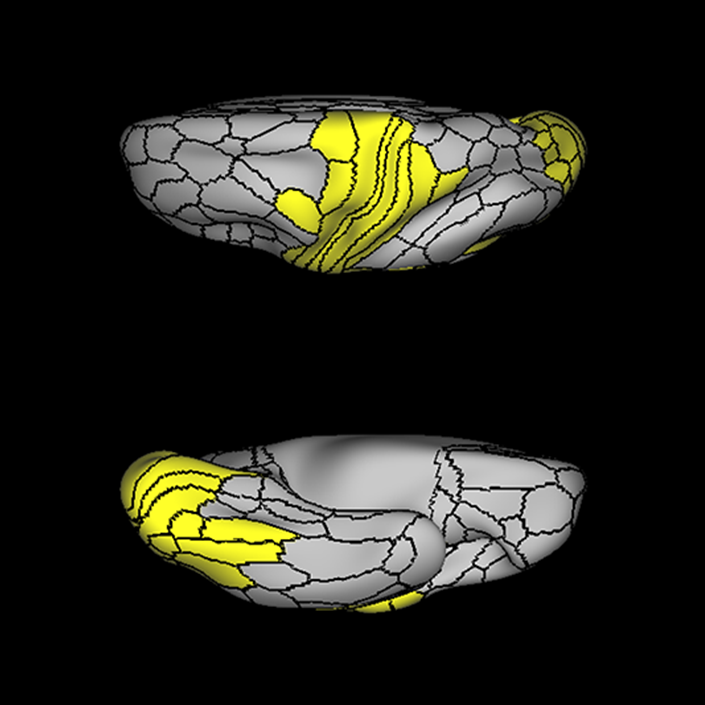

ᐅ SummaryArea 55b: part of the premotor areas. Relatively uncharacterized regions. In 1956, one of the only studies to characterize this regions concluded that the area played a role in language processing. ᐅ Where is it?Area 55b is located on the anterior half of the precental gyrus, approximately half way down its length along the convexity, just inferior to FEF. It also forms the adjacent floor of the precentral sulci and straddles slightly onto the posterior edge of the middle frontal gyrus. ᐅ What are its borders?Area 55b borders area FEF superiorly and PEF and area 6v inferiorly. Area 4 is its posterior border and areas 8AV and 8C form its anterior border across the precentral sulcus. ᐅ What are its functional connections?Area 55b demonstrates functional connectivity to area 4 in the motor strip, areas SCEF and SFL in the premotor areas, areas IFSp, IFJa, 8AV, 44, 45, and 47L in the lateral frontal lobe, areas STSda and STSdp in the temporal lobe, areas PSL and STV in the posterior opercular cortices, and area TPOJ1 in the lateral occipital lobe. ᐅ What are its white matter connections?Area 55b is structurally connected to the contralateral hemisphere and the superior longitudinal fasciculus. Contralateral connections course through the body of the corpus callosum to 6ma, 6a and 6mp. Connections with the superior longitudinal fasciculus connect 55b to parcellations PHT and PFm, and this tract terminates eventually in the temporal lobe at TGd. Local short association fibers connect with 8Av, 8C, IFJp, 3a, 3b and PEF. ᐅ What is known about its function?Area 55b is a relatively uncharacterized region. In 1956, one of the only studies to characterize this region concluded that the area played a role in language processing. |

A: lateral-medial

B: anterior-posterior

C: superior-inferior

ᐅ SummaryArea IFJa (inferior frontal junction, anterior): part of the lateral frontal lobe. Areas in the midventrolateral prefrontal cortex interact with posterior areas of the brain to retrieve specific auditory memories. The inferior frontal junction, in particular, serves as an important crossroads between bottom-up and top-down processing in the lateral prefrontal cortex. ᐅ Where is it?Area IFJA is located in the posterior portion of the inferior frontal sulcus. It comprises part of the inferior bank of the MFG in its upper portions. It is roughly superior to the pars opercularis portion of the inferior frontal gyrus. ᐅ What are its borders?Area IFJa borders area IFSp anteriorly and IFJp posteriorly. Its inferior border is area 44 and its superior border is area 8C. ᐅ What are its functional connections?Area IFJa demonstrates functional connectivity to areas 44, IFSa, IFSp, IFJp, and p9-46v in the dorsolateral frontal lobe, area SCEF in the medial frontal lobe, areas FEF, 55b PEF and 6r in the premotor areas, area FOP5 and PSL in the insular opercular regions, areas PH, PHT, and TE2p in the temporal lobe, areas MIP, TPOJ1, and LIPd in the inferior parietal lobe, and no areas in the medial parietal lobe. ᐅ What are its white matter connections?Area IFJa is structurally connected with the arcuate/SLF and surrounding parcellations. Connections with the arcuate/SLF project posteriorly and wrap around the Sylvian fissure to the middle and inferior temporal gyrus to end at TE1a, TE1m, and TE2a. There are also fibers that project superiorly form IFJa to end at SFL. These fibers are likely portions of the frontal aslant tract which has the majority of its inferior terminations at 44, a neighbor of IFJa. Local short association bundles connect to 8c, IFJa, IFSp, 44 and 8A. ᐅ What is known about its function?Areas in the midventrolateral PFC interact with posterior areas of the brain to retrieve specific auditory memories. The IFJ, in particular, serves as an important crossroads between bottom-up and top-down processing in the lateral prefrontal cortex. |

A: lateral-medial

B: anterior-posterior

C: superior-inferior